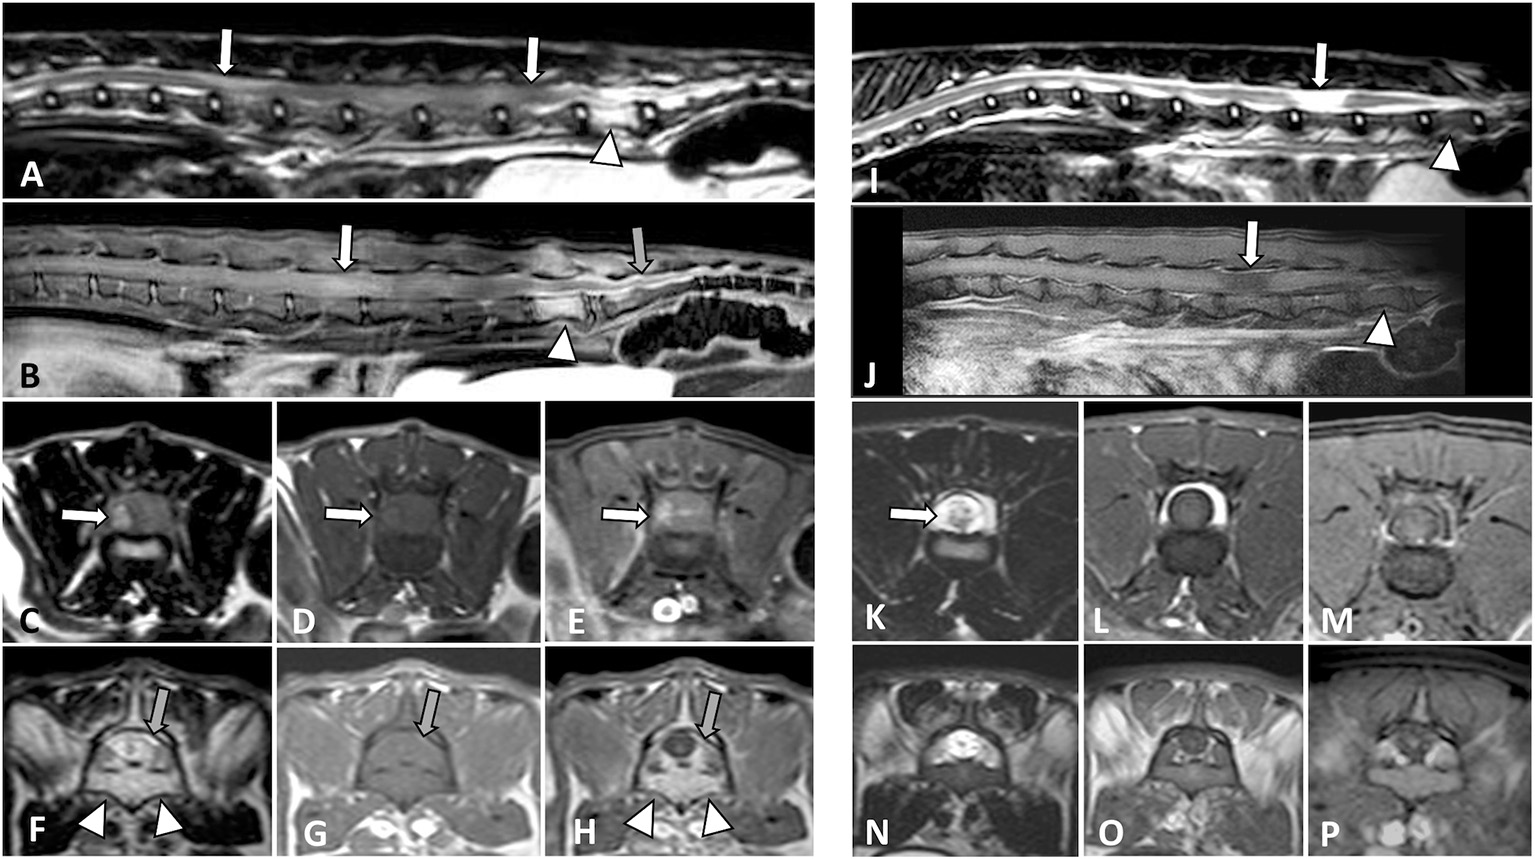

Two separate lesions, one epidural extending from the conus medullaris to the first coccygeal vertebrae and another intramedullary lesion extending from the L2 vertebra to the conus medullaris were found in 1/27 (3.7%) cases (Figures 1A–H). The cat was treated with chemotherapy (COP protocol) with improvement, in a control MRI that was done 3 months later a residual intramedullary malacic lesion on the L5 vertebra was the only relevant finding (Figures 1I–P) (case 4 in Table 3). At 9 months, an MRI of the head was done due to recent diffuse intracranial signs, showing a diffuse and intense meningeal enhancement compatible with lymphomatous meningitis. Further studies were not allowed by the owners.

Figure 1

MRI studies of a 1-year-old domestic short-haired paraplegic cat. A multifocal large cell lymphoma with an intramedullary lumbosacral lesion and a sacrococcygeal epidural lesion was diagnosed. On T2W sagittal plane (A) the spinal cord is swollen with an increased heterogeneous signal from L2 to L6 vertebrae (arrows). On T1W post-contrast SPIR sagittal plane (B) there is a diffuse intramedullary contrast enhancement (white arrow) and an intense epidural enhancement from L7 to the first coccygeal vertebrae (gray arrow). On transverse planes at the level of L4-L5 vertebrae, the spinal cord appears swollen due to an intramedullary lesion with a right component which is hyperintense on T2W (C), isointense on T1W (D), and shows heterogeneous enhancement on post-contrast SPIR (E) images. On transverse planes at the level of the L7 vertebra, there is an epidural infiltrative lesion hyperintense on T2W and isointense on T1W images (gray arrows in F,G, respectively) with intense post-contrast enhancement (gray arrow in H). An increased signal of the L7 bone marrow with cortical sparing is observed (arrowheads in A,B,F,H). After chemotherapy and clinical improvement, an MRI was performed at 3 months (I–P). On the sagittal planes (I, T2W; J, T1W post-contrast SPIR) the L7 bone marrow signal was normalized (arrowheads) and a malacic lesion, presumptively residual, was present along the L5 vertebra (arrows). On transverse planes at the level of L4-L5 vertebrae (K, T2W; L, T1W and M, T1W post-contrast SPIR), the previous intramedullary lesion was not observed, and signs of malacia were seen (arrow in K). The corresponding L7 vertebra transverse planes (N–P) did not show epidural changes.